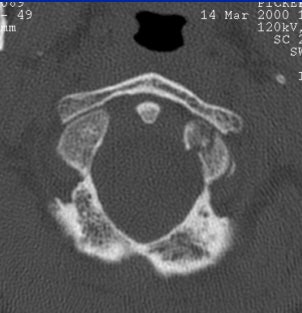

Whichever model is chosen, Cinnamon advised paying attention to the inverse relationship of contrast and spatial resolution, using the following case as an example (images F-G).

![]() |

| Image F |

"On the 2.5-mm slice, you can see the occipital condyle fracture. If (you) go down to the 0.5-mm slice, you can see the fracture just as well -- maybe it looks a little sharper. But you can still identify the fracture on the thicker slice. The value for this is on the coronal and sagittal reformatted images from the 2.5-mm axials. There's a tremendous amount of stair-step artifacts. On the 0.5-mm images, you've eliminated the stair-step artifact because your spatial resolution is so good."